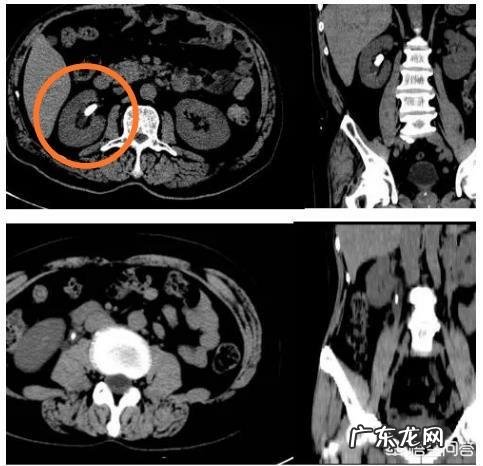

上图是一位肾结石患者的CT图像 , 可以看到右肾肾盂有一颗高密度阳性结石 , 冠状位看的也非常清晰 。